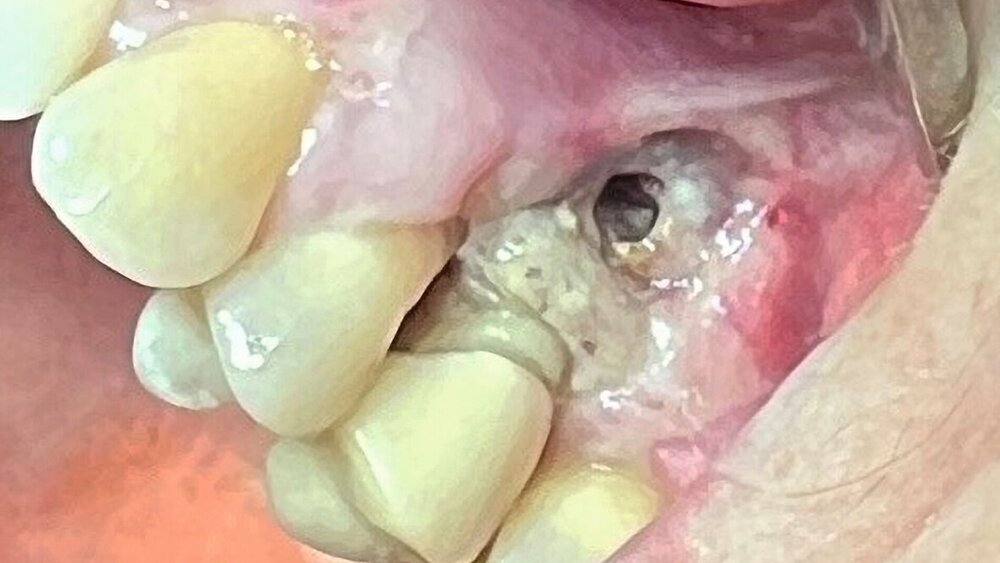

Klinisch zeigte sich derZahn 25 perkussionsempfindlich mit Lockerungsgrad II (der ja bereits vor der Wurzelbehandlung vorhanden war). Der umgebende Knochen war exponiert und nekrotisch, jedoch schmerzfrei (Abbildung 1). Der Vitalitätstest mit Kältespray ergab keine Reaktion an Zahn 24, während die Zähne 26 und 23 vital reagierten. Aufgrund der ausgedehnten Nekrose und der vorhandenen Zahnlockerung entschieden wir uns im Einvernehmen mit der Patientin für die chirurgische Entfernung des Zahnes sowie des nekrotischen Hart- und Weichgewebes. Die Patientin wurde ausführlich über die Risiken des Eingriffs (Schmerzen, Schwellung, Nachblutung, Nervverletzung, mögliche Eröffnung der Kieferhöhle, Schädigung benachbarter Strukturen) aufgeklärt und erhielt einen entsprechenden Aufklärungsbogen.